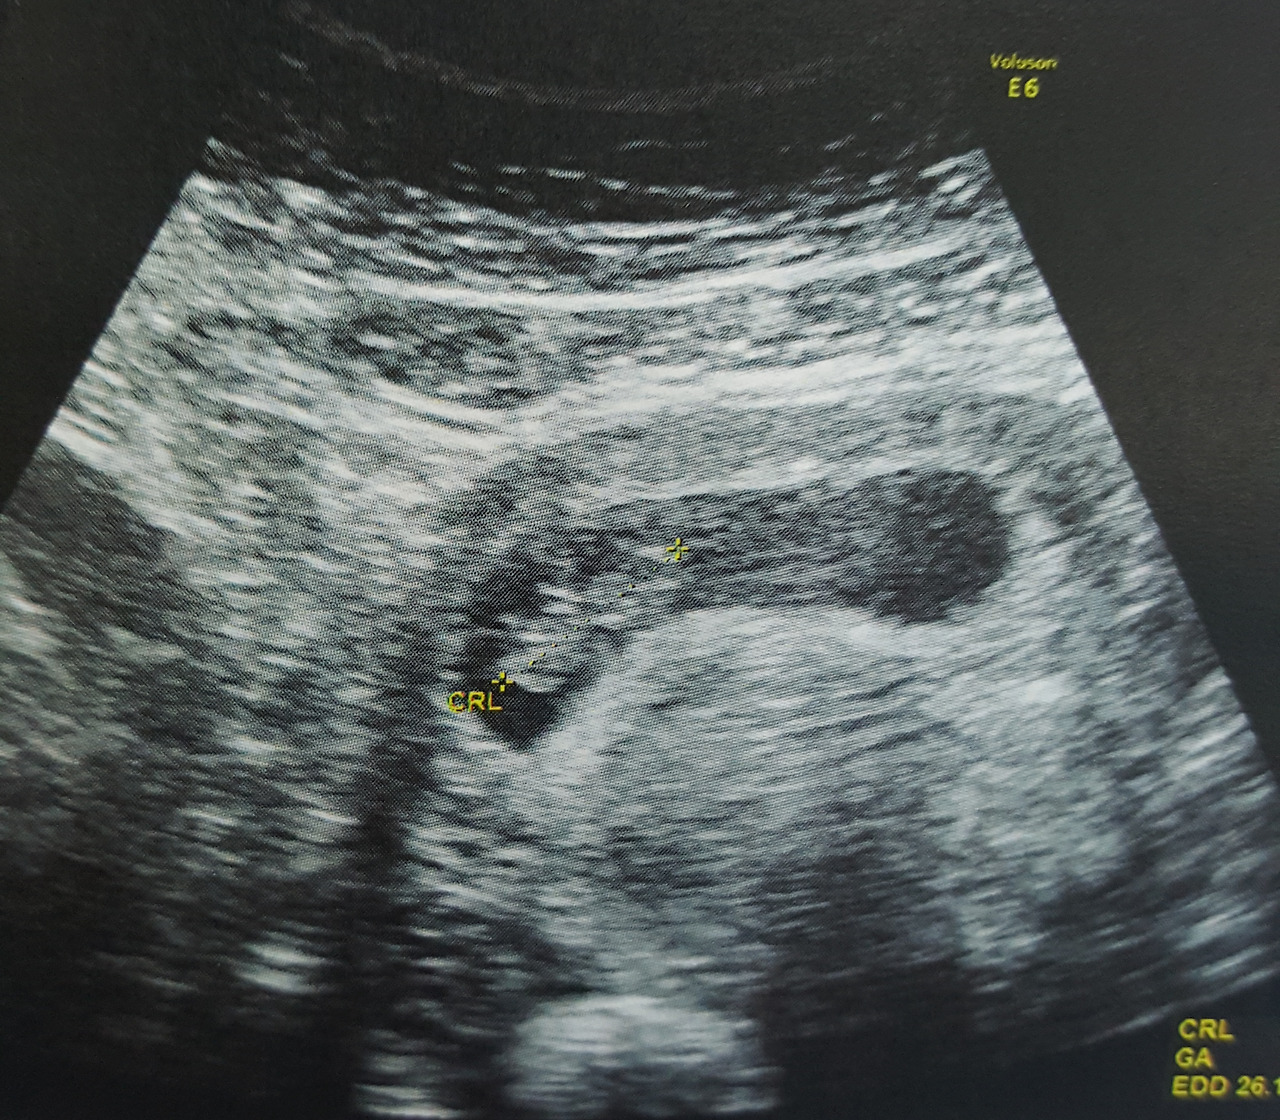

정말 새로운 곳에서 몸과 마음이 편해서일까. 휴가를 다녀온 후 사무실로 복귀 후 며칠 뒤에 아내에게서 전화가 왔다. 흥분되고 울먹이는 목소리로. 처음엔 무슨 사고가 난 줄 알았는데 드디어 임신을 했다는 세상에서 가장 큰 선물을 나에게 안겨주었다. 마음고생 많았던 아내는 수화기를 통해 엉엉 울었다. 이렇게 기쁠수가.

하루하루 점점 배가 불러오는 모습을 보면서 한편으로는 걱정이 되었다. 한국이 아닌 태국에서 병원을 다녀야하기에. 말도 제대로 통하지 않는데. 초반에는 태국에서 병원을 다녔지만 출산 가까이 와서는 한국으로 병원을 다녔다. 혼자 비행기를 타고, 임신한 몸으로.

출산 예정일이 다가왔을 때 아내는 혼자 한국으로 향했다. 이제는 태국에 같이 있을 수가 없었다. 배속에 있는 아이는 아빠가 보고 싶었는지 거꾸로 자라고 있었다. 이것 때문에 제왕절개 수술을 할 수밖에 없었고 정해진 수술날짜에 맞춰 휴가를 나올 수 있었다. 만약 자연분만이었으면 시간 맞추기가 어려웠을텐데. 그때나 지금이나 나를 잘 따르는 우리 딸이 태어나기도 전부터 아빠를 너무나 보고 싶어했던 것 같다. 하루라도 더 같이 있고 싶어서.